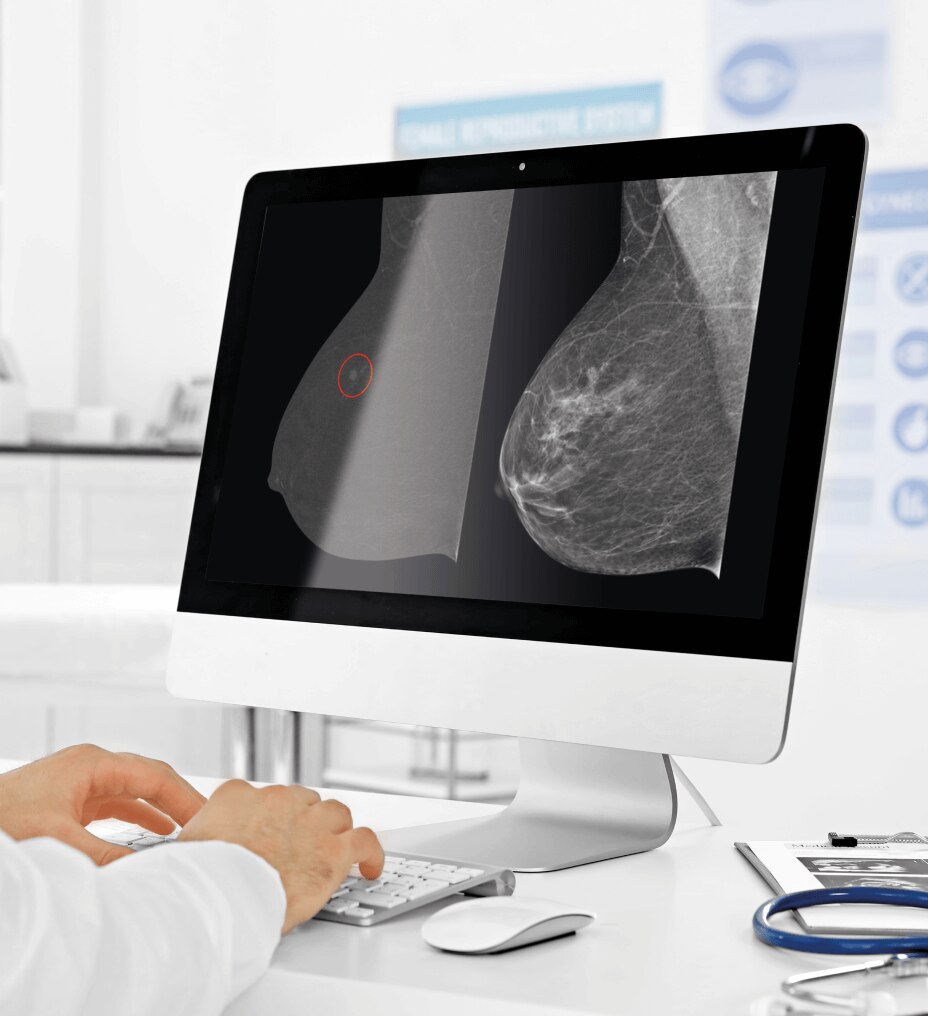

Modulación de dosis de órgano (ODM): consigue una dosis de radiación reducida en hasta un 40 % mediante la modulación de la corriente del tubo de rayos X en tejidos y órganos superficiales como las mamas, y mantiene la calidad de diagnóstico y la productividad.